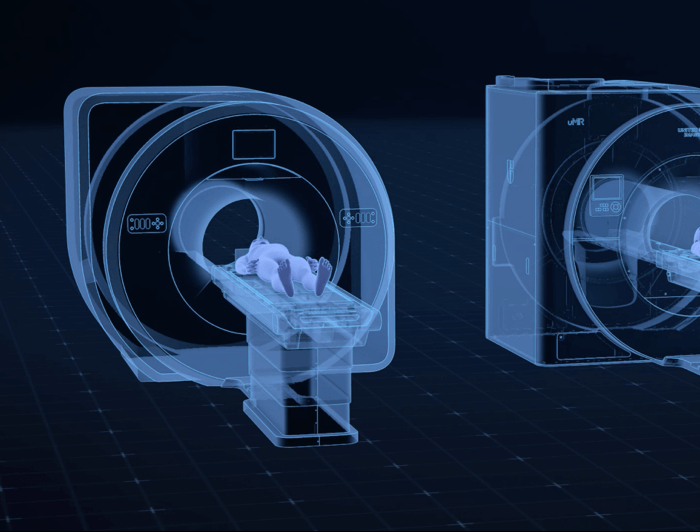

智云磁体

自主研发的匀场技术,优异的磁场均匀度。

智云梯度

智能涡流补偿技术,高梯度性能。